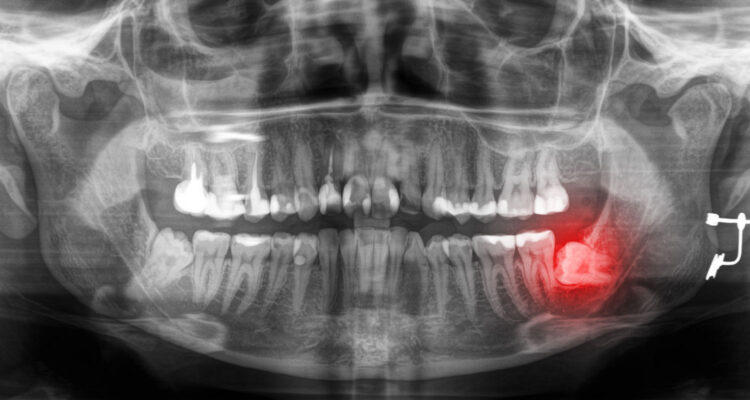

Что такое ретинированные зубы мудрости?

Ретинированный зуб мудрости – это зуб, коронка которого по тем или иным причинам не прорезалась полностью. Ретенция бывает полной — когда коронка полностью находится в альвеолярной кости или неполной — когда коронка частично или полностью находится под слизистой десен.

Полная ретенция

Видалення зубів мудрості. Часті питання

Неполная ретенция